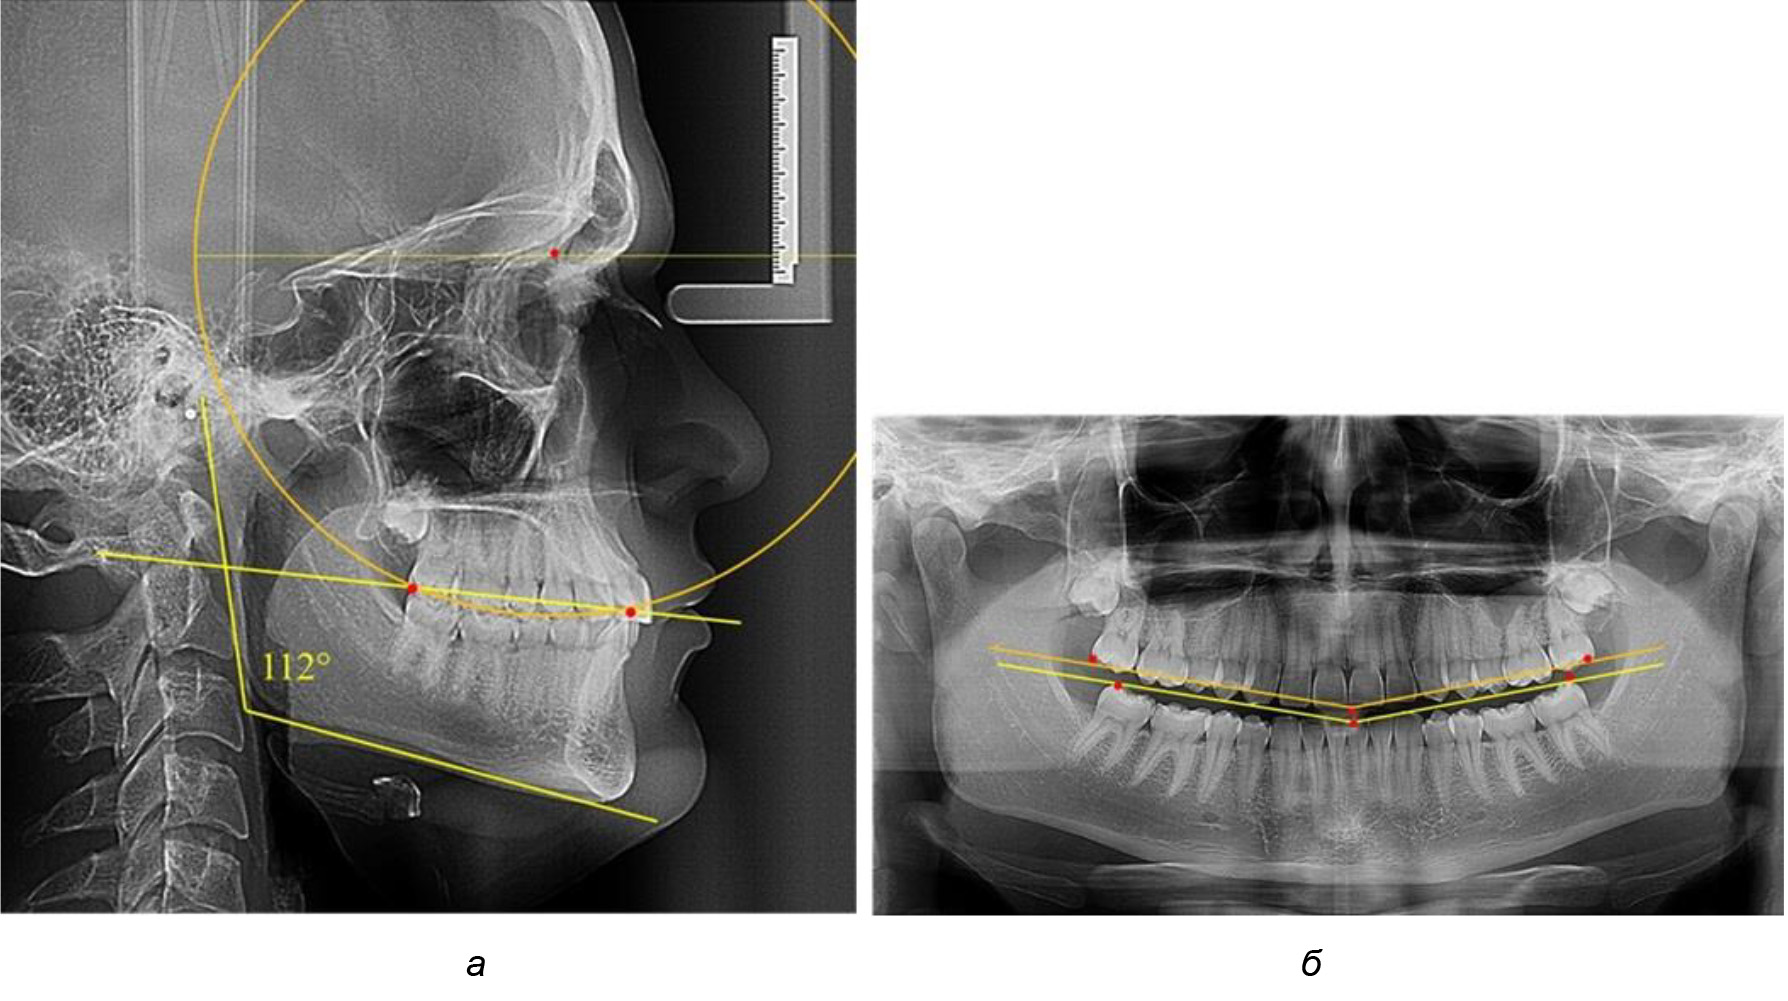

В 3-ю подгруппу вошли ТРГ и ОПТГ 14 человек 1-й группы, что составило (22,58 ± 5,31) % от общего количества людей 1-й группы. Величина угла нижней челюсти в среднем составила (114,85 ± 2,87)° и характеризовала горизонтальный тип нижней челюсти.

Глубина кривой Spee в среднем по 2-й подгруппе составил (2,94 ± 0,47) мм, что было меньше, чем в других подгруппах. Деление величины радиуса круга к длине окклюзионной линии составило 1,616 ± 0,02 (рис. 4).

Рис. 4. Особенности кривой Spee на ТРГ (а) и ОПТГ (б) у людей с горизонтальным типом лица